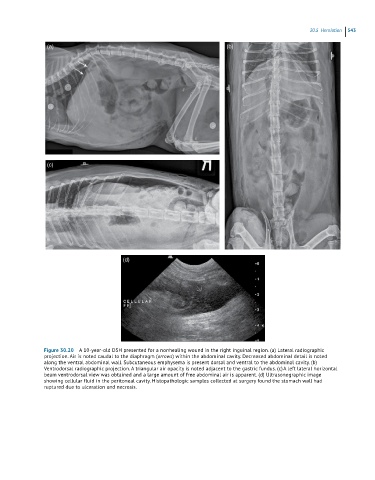

Figure 30.20 A 10-year-old DSH presented for a nonhealing wound in the right inguinal region. (a) Lateral radiographic

projection. Air is noted caudal to the diaphragm (arrows) within the abdominal cavity. Decreased abdominal detail is noted

along the ventral abdominal wall. Subcutaneous emphysema is present dorsal and ventral to the abdominal cavity. (b)

Ventrodorsal radiographic projection. A triangular air opacity is noted adjacent to the gastric fundus. (c) A left lateral horizontal

beam ventrodorsal view was obtained and a large amount of free abdominal air is apparent. (d) Ultrasonographic image

showing cellular fluid in the peritoneal cavity. Histopathologic samples collected at surgery found the stomach wall had

ruptured due to ulceration and necrosis.